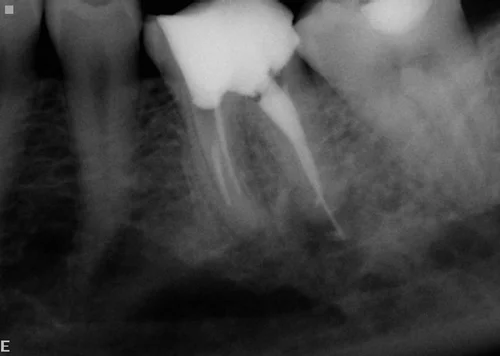

This shows an infected premolar with bone loss around the root; and a failed attempt at root treating a molar, with extensive bone loss. A decision was made to root treat the teeth and restore them.

The lower left premolar was root filled and turned out to have an unusual forked root structure ('bifid canal'). The infected molar root was re-root filled and a new crown made, saving both teeth.